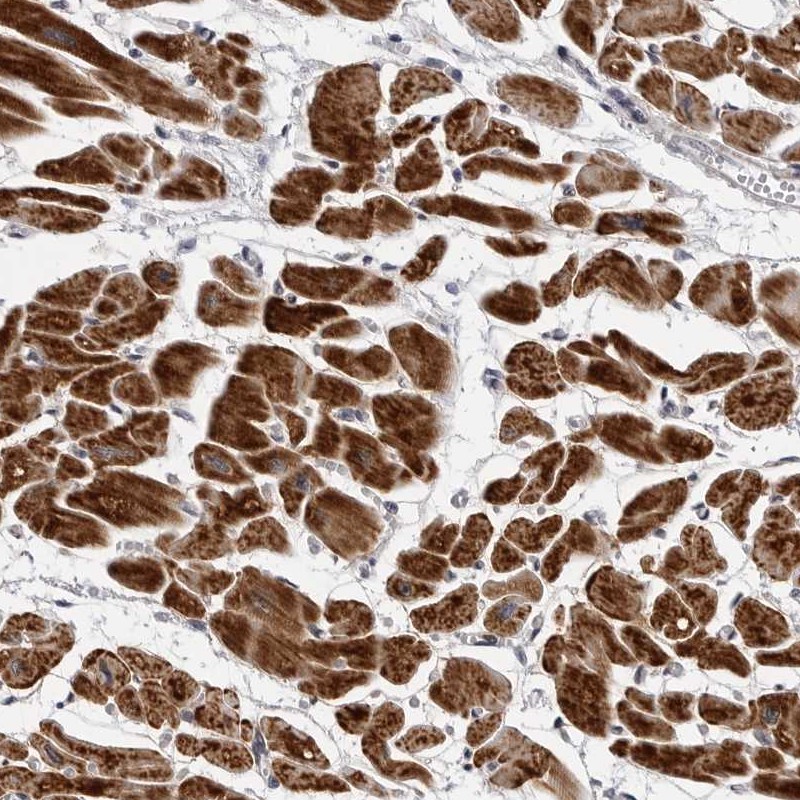

Immunohistochemical staining of human heart muscle shows strong cytoplasmic positivity in myocytes.